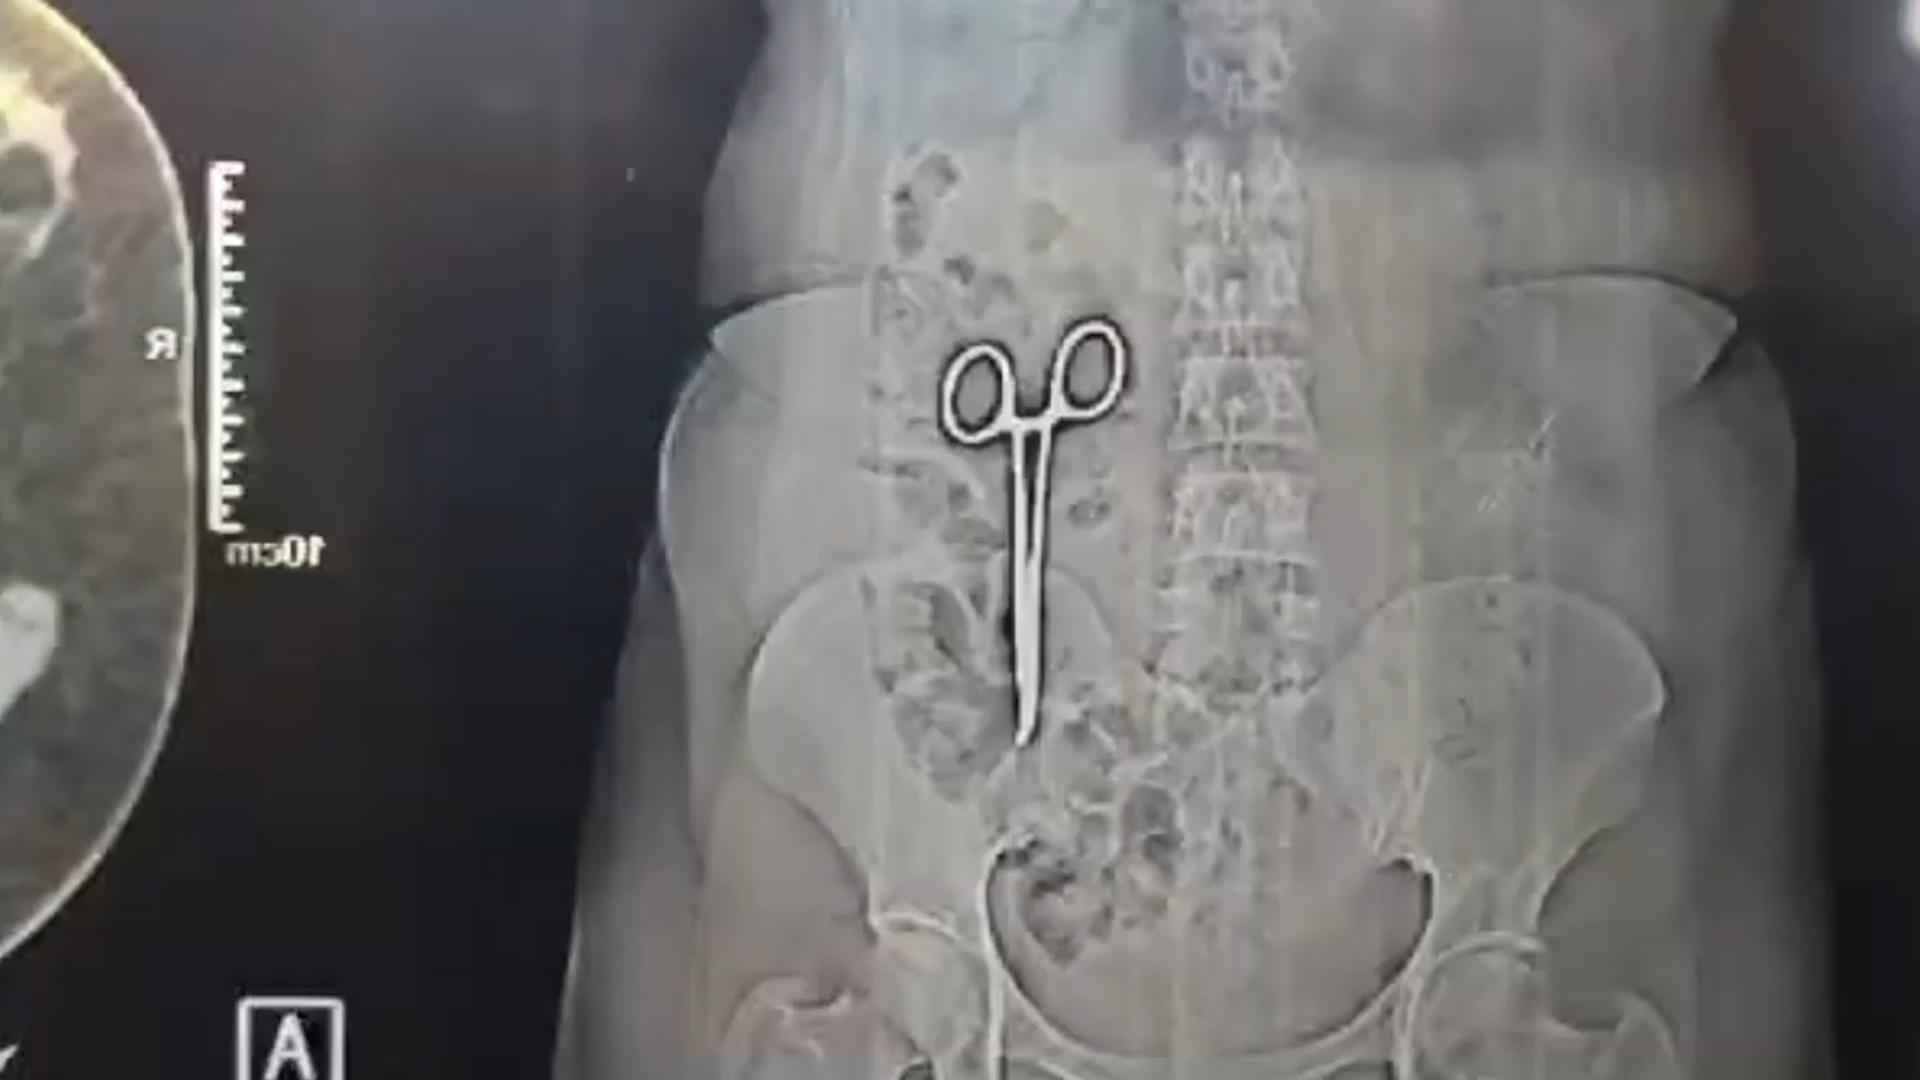

據英國鏡報報道,這名來自中央邦的44歲婦女卡拉白在2022年的2月曾接受手術切除胃部的癌症腫塊,手術成功,然而卡拉白自那時就持續腹痛。為了找出病因,卡拉白看了許多醫生,也在醫院中做了各種檢查,最後才在她的結腸裡發現一個金屬物體,結果證實是醫療用剪刀,痛了2年的原因是醫院外科團隊在手術過程中不小心在她的腹部留下了一把剪刀。